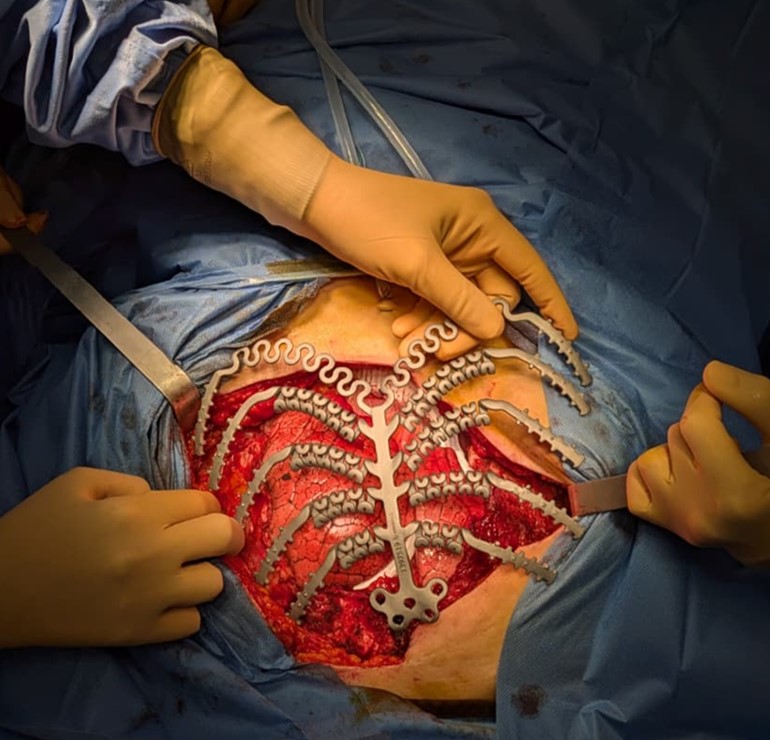

Surgical Treatment of Chest Wall Tumours

Malignant tumours of the chest wall are extremely rare and may arise from primary bone tumours or bone metastases from other tumours (e.g. breast, ovary, uterus, lung). The complexity of their treatment depends on: a) their rarity (which makes it difficult to establish a general treatment protocol); b) their possible extensiveness (which generally requires very wide surgical resection); c) the difficulty of reconstruction after large resection and d) possible post-operative complications.Particular attention must be given during the reconstruction to restoring wall rigidity, using titanium prostheses that may even be created “ad hoc” for the patient, based on pre-operative radiographic studies (CT or MRI).

Active collaboration with colleagues from the Plastic Surgery Unit in Modena Policlinico makes it possible to perform the reconstructive phase in the best possible manner, with adequate muscle transposition to cover the prosthesis, with the aim of avoiding its possible infections.Over the last three years, the Thoracic Surgery Unit in Baggiovara has performed several interventions for tumours of the chest wall. Of particular interest were two recent sternum replacements with titanium prostheses, for mediastinal seminoma and ovarian tumour metastases.The clinical research project for these pathologies involves increasingly close collaboration with oncologists and radiotherapists in order to standardise the clinical treatment protocol. Similarly important is the collaboration with companies that produce titanium prostheses, with the aim of studying the clinical effects of prosthesis placement on the chest wall over time.